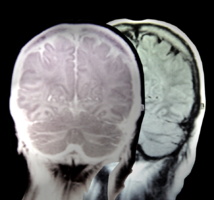

Lo que han descubierto ahora los científicos de la UCI es que las personas con hepertimesia tienen un cerebro particular. Según la investigadora Aurora LePort, autora principal del actual estudio, así “estamos consiguiendo dar forma a una explicación coherente y descriptiva de lo que sucede”. LePort trabaja en el Centro de Neurobiología del Aprendizaje y la Memoria de la UCI.

En concreto, los científicos han comprobado que los individuos hipertimésicos analizados presentan variaciones en nueve estructuras cerebrales, en comparación con otros sujetos de control.

Una de estas variaciones consiste en una materia blanca más sólida en la conexión entre las partes media y delantera del cerebro.

En general, la mayoría de las diferencias cerebrales halladas están situadas en áreas del cerebro que se sabe están relacionadas con la memoria autobiográfica, explican los científicos.